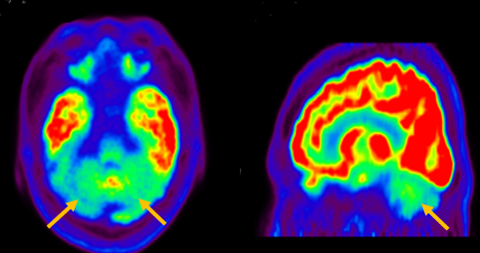

다계통 위축이란 뇌의 다양한 계통에서 위축이 발생하는 것을 의미합니다. 파킨슨 증상이 있으면서 질병 초기에 소변 장애나 기립성 저혈압으로 인한 어지러움이 두드러지게 나타나는 경우, 보행 시 비틀거림이나 구음 장애와 같은 소뇌 위축에 따른 운동 실조 증상이 나타나는 경우, 꿈에서 하는 행동을 수면 중에 보이는 렘수면 행동 장애가 동반되는 경우 다계통 위축을 의심합니다. 다계통 위축은 파킨슨병과 달리 안정 시 떨림이 잘 보이지 않고, 증상이 대칭적인 경우가 많으며, 진행이 빠르며, 레보도파와 같은 항파킨슨 약제에 잘 반응하지 않습니다. 다계통 위축은 뇌 자기공명영상(MRI)에서 교뇌에 십자 모양의 고음영이 나타날 수 있는데, 이를 십자무늬 빵(hot cross bun) 징후라고 합니다. 또한 초기에서는 뇌 자기공명영상(MRI)이 정상으로 보이더라도 뇌포도당 양전자 단층촬영(PET)에서는 소뇌 또는 기저핵의 대사 기능이 저하된 상태가 관찰될 수 있습니다. 이러한 영상 소견은 특징적인 임상 증상과 함께 진단에 참고할 수 있습니다.

[다계통위축 환자의 뇌자기공명영상에서 확인되는 십자무늬빵 징후]

[다계통위축 환자의 뇌포도당 양전자 단층 촬영에서 확인되는 소뇌의 대사 기능 저하]